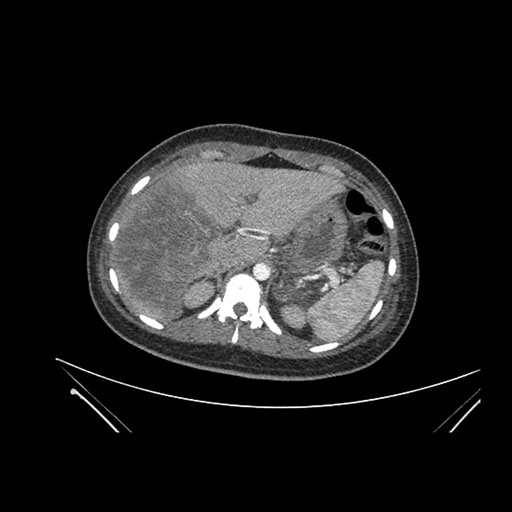

Look through the patient's CT scan to identify any areas of concern for the necessary procedure.

Axial Venous